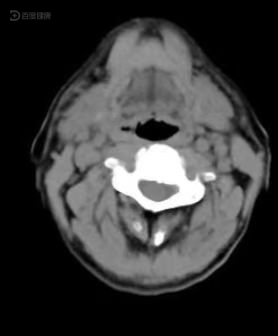

声门型喉癌的ct分析

声门旁间隙喉癌的诊断及治疗